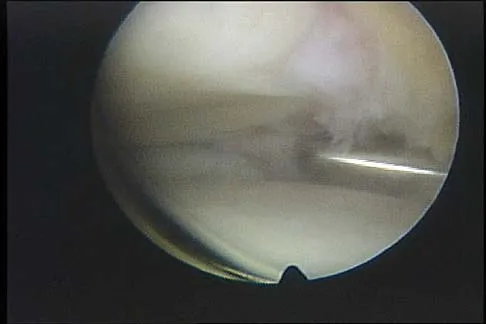

Figure 43 shows an arthroscopic view of a right shoulder through a lateral portal in the beach chair position. The arrow is pointing to what structure?

Explanation

This view from the lateral portal shows a full-thickness rotator cuff tear. The glenohumeral joint can be visualized through this tear. The glenoid, labrum, and biceps tendon attaching to the superior aspect of the glenoid are easily viewed from this portal, and the arrow is pointing to the biceps tendon. Arthroscopic rotator cuff repair can be performed while visualizing from this portal and using anterior and posterior working portals. Mazzocca AD, Noerdlinger M, Cole B, et al: Arthroscopy of the shoulder: Indications and general principles of techniques, in McGinty JB (ed): Operative Arthroscopy, ed 3. Philadelphia, PA, Lippincott Williams & Wilkins, 2003, pp 412-427.